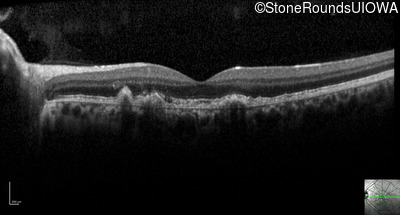

Optical Coherence Tomography - Left - 20/25 +2 sc

Exemplar / OCT Stack

Optical Coherence Tomography - Left - 20/20 +1 sc